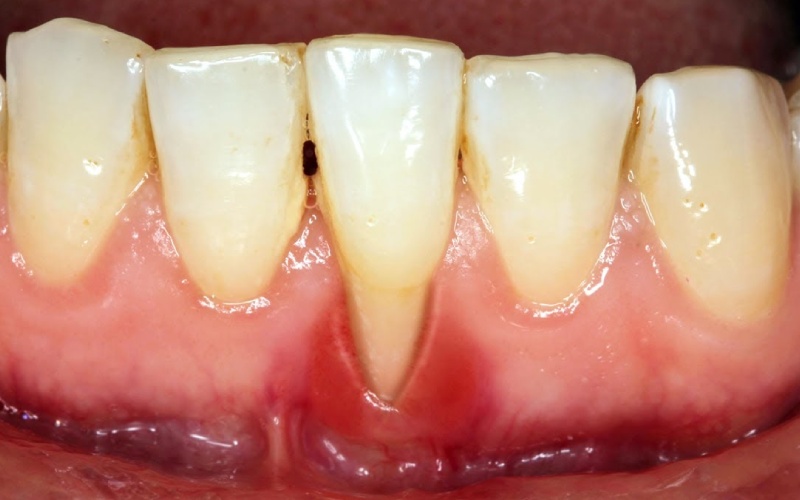

Tụt lợi hay còn gọi là tụt nướu, là một vấn đề răng miệng phổ biến nhưng không phải ai cũng quan tâm đến. Đây là hiện tượng phần nướu bao quanh chân răng có xu hướng di chuyển xuống cuống răng, làm lộ phần cổ chân răng. Hiện tượng này có thể chỉ xảy ra ở một răng nhưng cũng có thể một vài răng hoặc nguyên cả hàm trên và dưới.

- Lợi bị rút lại làm lộ cổ chân răng, kiến răng trông dài hơn so với bình thường.

- Vùng lợi bị tụt sưng đỏ hơn so với các vùng lợi khác và gây đau nhức, khó chịu.

- Thường xuyên xuất hiện tình trạng chảy máu chân răng, nhất là khi chải răng, sử dụng chỉ nha khoa.

Vôi răng là nguyên nhân hàng đầu gây nên tình trạng tụt lợi. Khi không vệ sinh răng miệng sạch sẽ, thức ăn thừa và mảng bám tích tụ nhiều trên răng và sẽ dần bị vôi hóa thành vôi răng, bám cứng chắc trên bề mặt răng và bên dưới lợi. Đây chính là nơi cư trú lý tưởng của các vi khuẩn có hại và chúng sẽ tấn công mô lợi, gây viêm nhiễm và làm cho lợi tuột dần xuống.